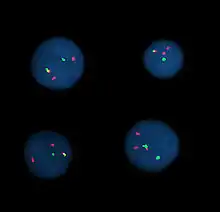

Інтерфазні клітини, в яких візуалізовано хромосомна перестановка t(9;22) за допомогою FISH

Флюоресцентна гібридизація in situ (англ. Fluorescence in situ hybridization, FISH) — це цитогенетичний метод, який використовується для визначення і локалізації певної послідовності ДНК на хромосомі. Для досягнення цієї мети використовуються спеціальні гібридизаційні ДНК-зонди з флюоресцентними властивостями та комплементарні до певної ділянки ДНК. Використання FISH дозволяє визначати різноманітні хромосомні аномалії: делеції, транслокації, ампліфікації, тощо[1].